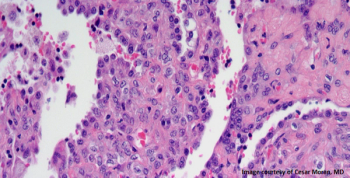

A 34-year-old woman presents with a coin lesion in the right upper lobe of the lung. What is your diagnosis?